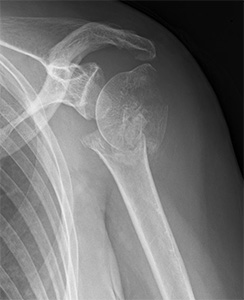

上腕骨近位部骨折(肩の骨折)

疾患と症状

高齢者の転倒時に肩や腕を強打して生じることが多い骨折です。

高齢化に伴い、発生数が増加しています。

必要に応じて地域の他病院と連携しながら、もとの日常生活への復帰を目指します。

• 画像:上腕骨近位部骨折

(術前)